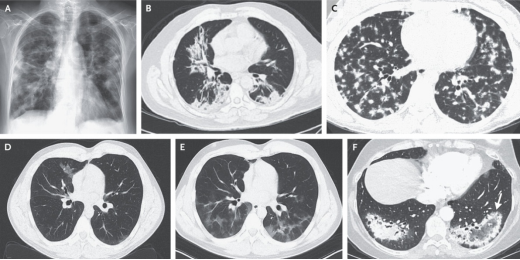

影像学上,COP的X线主要表现为双肺局灶或弥漫性实变影(图3A)。典型的CT征象为多发性实变影,多分布于双下肺、胸膜下或支气管血管束周围,可单侧或双侧,伴或不伴支气管充气征(图3B)。其他征象:①结节/肿块型:大小不等,单发或多发,可呈实性、部分实性或磨玻璃样。部分结节或肿块边界不清且有毛刺;也可为边界清楚、直径约8mm的腺泡型结节或边界不清、直径更小、弥漫分布的微结节(图3C);②游走性改变(图3D-E);③小叶周围型:小叶间隔增厚,胸膜下可见边界不清的弓形或多边形实变;④线状和带状影:平行或垂直于胸膜的曲线带;⑤反晕征或环礁征(图3F);⑥进行性纤维化或蜂窝样改变、纵隔淋巴结肿大和胸腔积液等较少见。

图3 COP的影像学表现

COP的影像学表现多样,其早期最常被误诊为感染性肺炎,因此,应对抗生素治疗无反应或效果差的“肺炎”提高警惕。结合临床背景并依据影像线索进行鉴别诊断后(表2),如拟诊为COP患者病情稳定,可考虑给予激素治疗并随访观察。若怀疑高风险疾病(如恶性肿瘤、血管炎等)或临床治疗效果与初步诊断相矛盾时,建议尽早完善组织病理检查,这也有助于我们进一步寻找继发因素。